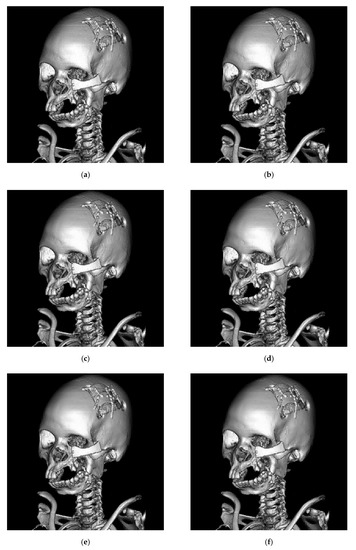

| Figure 6a | Figure 6b | Figure 6c | Figure 6d | Figure 6e | Figure 6f | Figure 6g | Figure 6h | ||

| AMBTC | HPSNR | 52.386 | 53.714 | 52.327 | 56.880 | 51.947 | 55.782 | 51.997 | 53.398 |

| MSSIM | 0.999989 | 0.999993 | 0.999991 | 0.999998 | 0.999988 | 0.999996 | 0.999989 | 0.999992 | |

| [17] | Payload | 47140 | 54040 | 53500 | 113620 | 90940 | 134800 | 86230 | 86755 |

| HPSNR | 45.627 | 47.150 | 46.046 | 50.836 | 45.050 | 48.919 | 45.290 | 46.766 | |

| MSSIM | 0.985399 | 0.989024 | 0.991863 | 0.996137 | 0.991472 | 0.997172 | 0.992645 | 0.992822 | |

| [20] | Payload | 56285 | 64040 | 62915 | 119825 | 100625 | 144560 | 95705 | 95885 |

| HPSNR | 45.305 | 46.676 | 45.621 | 49.429 | 44.617 | 47.689 | 44.828 | 46.192 | |

| MSSIM | 0.983738 | 0.986889 | 0.990008 | 0.990257 | 0.986442 | 0.98905 | 0.988244 | 0.988436 | |

| [22] | Payload | 47140 | 50404 | 53500 | 113560 | 90940 | 134800 | 86230 | 86695 |

| HPSNR | 45.619 | 47.085 | 46.040 | 50.655 | 45.044 | 48.920 | 45.287 | 46.753 | |

| MSSIM | 0.985352 | 0.988626 | 0.99183 | 0.995239 | 0.991359 | 0.997161 | 0.992628 | 0.992788 | |

| Ours | Payload | 101136 | 89360 | 105416 | 133600 | 123408 | 147720 | 122944 | 121792 |

| HPSNR | 52.848 | 53.871 | 52.551 | 57.262 | 53.136 | 56.705 | 53.175 | 54.594 | |